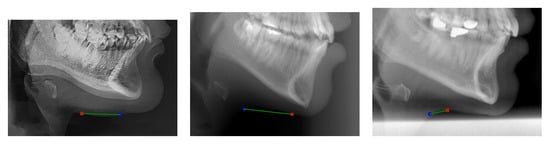

The landmark on the throat soft tissue, Th’, with the MRE error of more than 60 pixels, was detected the least accurately. This MRE is almost 2.5 times higher than for the second-least accurately detected landmark, Rh. For the cephalometric analyses conducted by the AUDAX company, the landmark Th’ defines just a point where a face profile ends at the bottom. The landmark Th’ has no other meaning in these analyses, and, consequently, it was annotated very carelessly. Figure 5 depicts three examples of Th’ landmark annotation and localization by the SCN-EXT method. It can be noticed that Th’ was annotated on three completely different parts of the throat (see blue circles). Accordingly, this means a poorer ability to learn this landmark and a higher radial error (see the green lines). To illustrate, if we omitted the Th’ landmark from the statistics, then the MRE for the SCN-EXT method decreases from 11.26 pixels (see Table 6) to 10.57 pixels, or decreases by 6.13%.

Figure 5. The worst-detected landmark Th’ by using the SCN-EXT method: three examples from the AUDAX database. Estimated landmarks are denoted by a red x, while ground-truth locations are superimposed as blue circles.